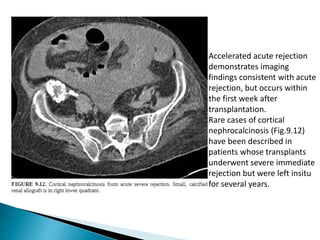

Accelerated acute rejection

demonstrates imaging

findings consistent with acute

rejection, but occurs within

the first week after

transplantation.

Rare cases of cortical

nephrocalcinosis (Fig.9.12)

have been described in

patients whose transplants

underwent severe immediate

rejection but were left insitu

for several years.